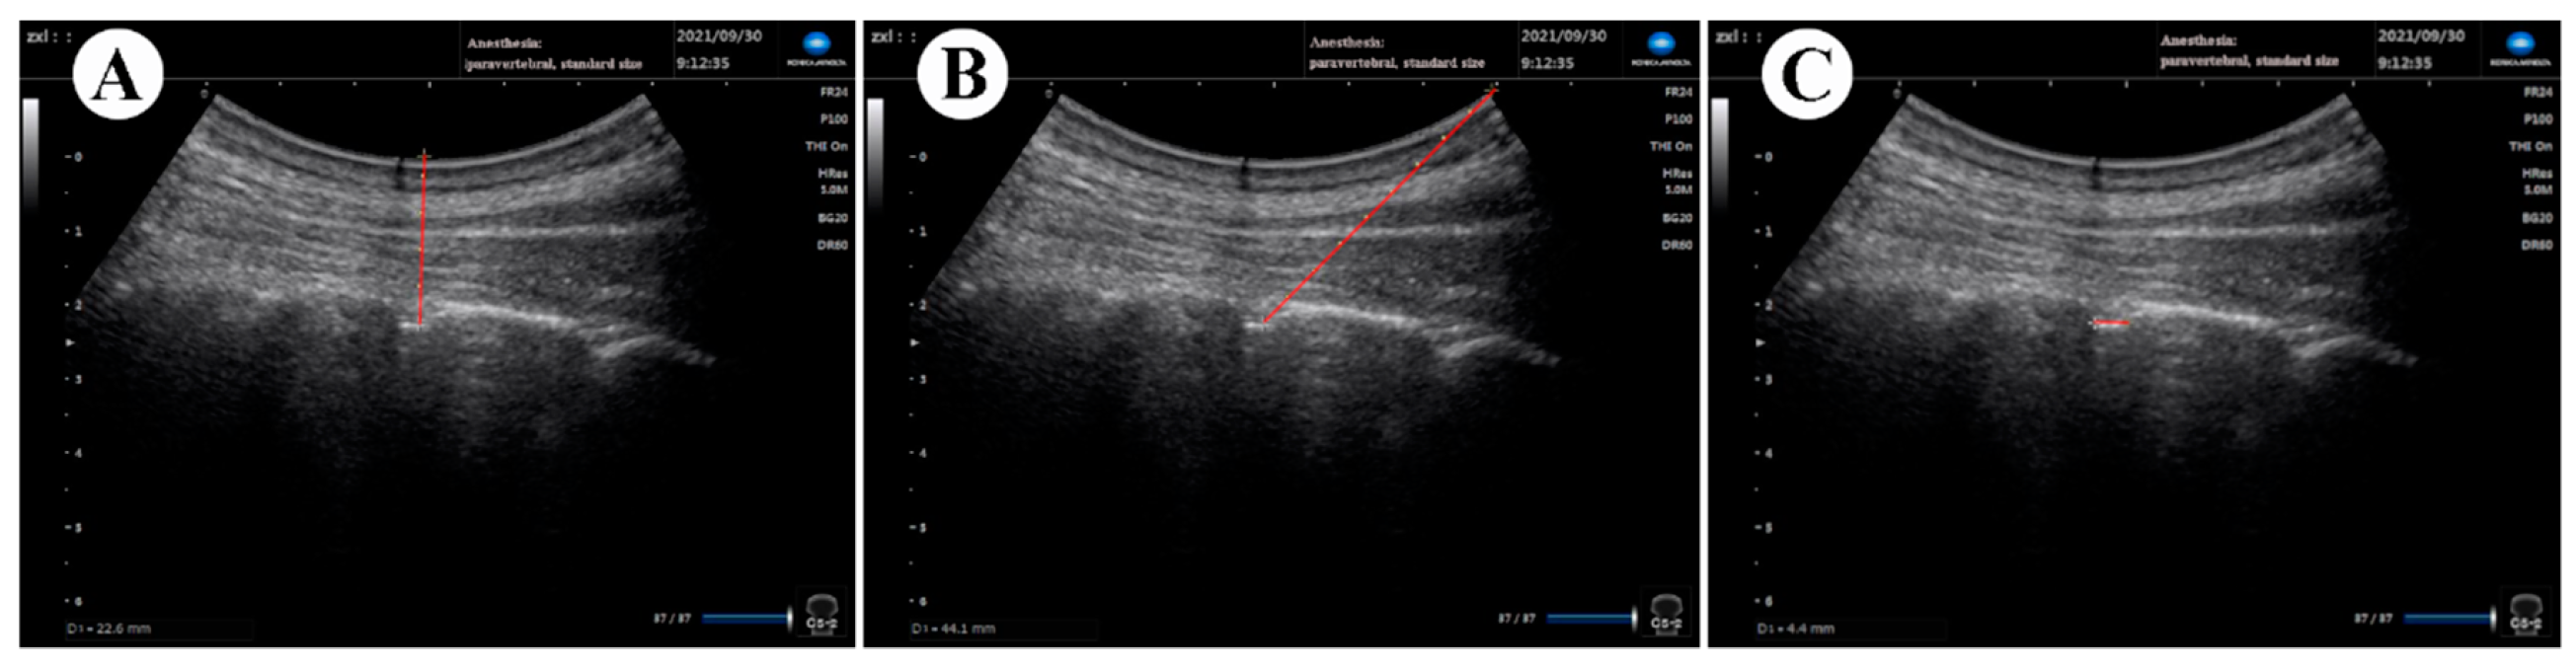

Figure 3.

Example of ultrasonic image measurement in comfortable position. Vertical (A) and oblique distances (B) from the skin to the posterior dura and width of the interlaminar space were also measured (C) using the relevant “frozen image” of the ultrasound.